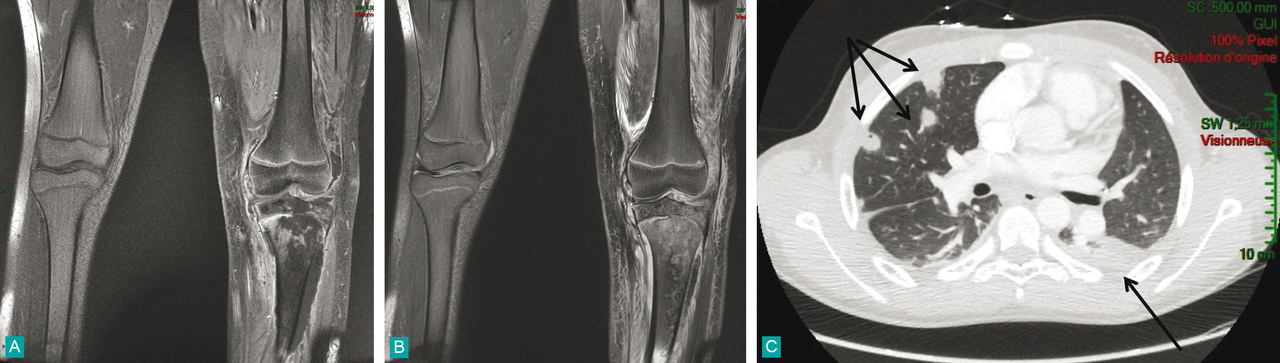

Garçon de 12 ans et demi ayant une ostéomyélite du tibia supérieur associée à une arthrite infectieuse du genou dans un contexte de septicémie à S. Aureus metis producteur d'une toxine de panton-valentine.A. IRM coronale en séquence T1 Fatsat avec injection de gadolinium.B. IRM coronale en séquence T2 Fatsat montrant un hypersignal hétérogène de l'extrémité supérieure du tibia en faveur d'une ostéomyélite étendue du tibia compliquée d'un abcès sous périosté métaphyso-diaphysaire latéral tibial et d'un épanchement intra-articulaire du genou gauche.C. Scanner thoracique montrant des condensations centimétriques parenchymateuses sous-pleurales en faveur d'abcès pulmonaires avec présence d'un épanchement pleural bilatéral modéré prédominant à gauche.